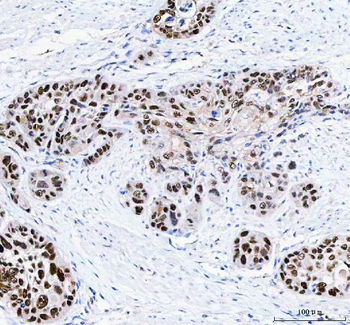

![Anti-FEN1 [SAIC-21C-4]](/images//pub/media/catalog/product/NewWebsite/35/orb1089994_1.png)

![Anti-FEN1 [SAIC-21C-4]](/images/pub/media/catalog/product/NewWebsite/35/orb1089994_2.png)

![Anti-FEN1 [SAIC-21C-4]](/images/pub/media/catalog/product/NewWebsite/35/orb1089994_3.png)